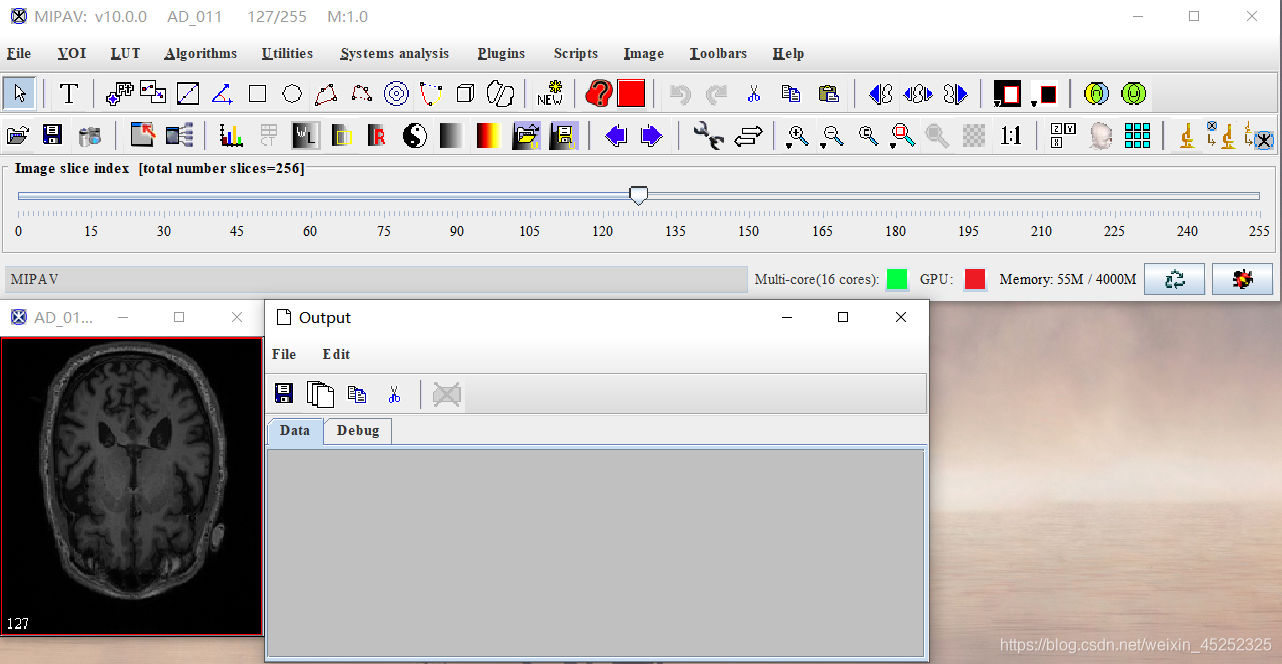

1、打开MIPAV并选择预处理图片(.nii格式):

点击file-open image (A) form disk选择需要处理的文件

2、点击algorithm-brain tools-Talairash transformer